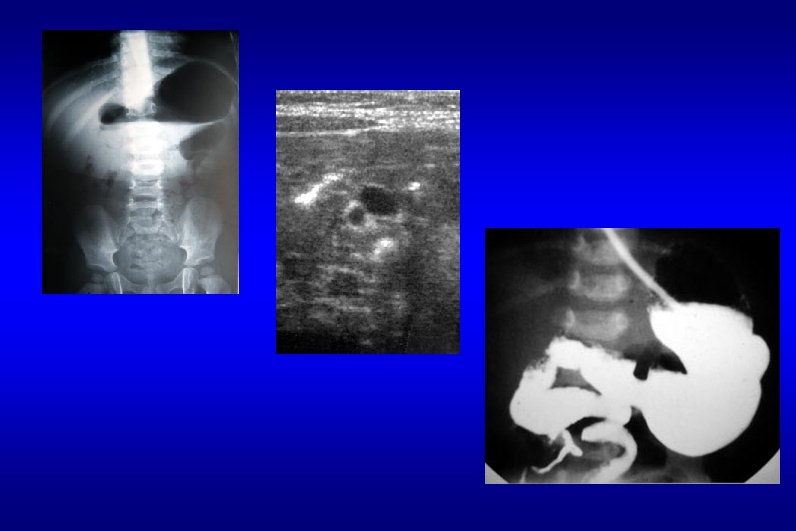

Diagnostic étiologique • 2 - ONN fonctionnelles a - Maladie de Hirschsprung • « Mégacolon congénital » • absence de cellules ganglionnaires des plexus nerveux de la paroi intestinale responsable d ’une absence de péristaltisme et d ’une spasticité OCCLUSION

Diagnostic étiologique • touche toujours le rectum et s ’étend plus ou moins haut sur le colon : 75% sont des formes rectosigmoïdiennes

Diagnostic étiologique • Diagnostic : ballonnement +++ , vomissements BIOPSIES +++